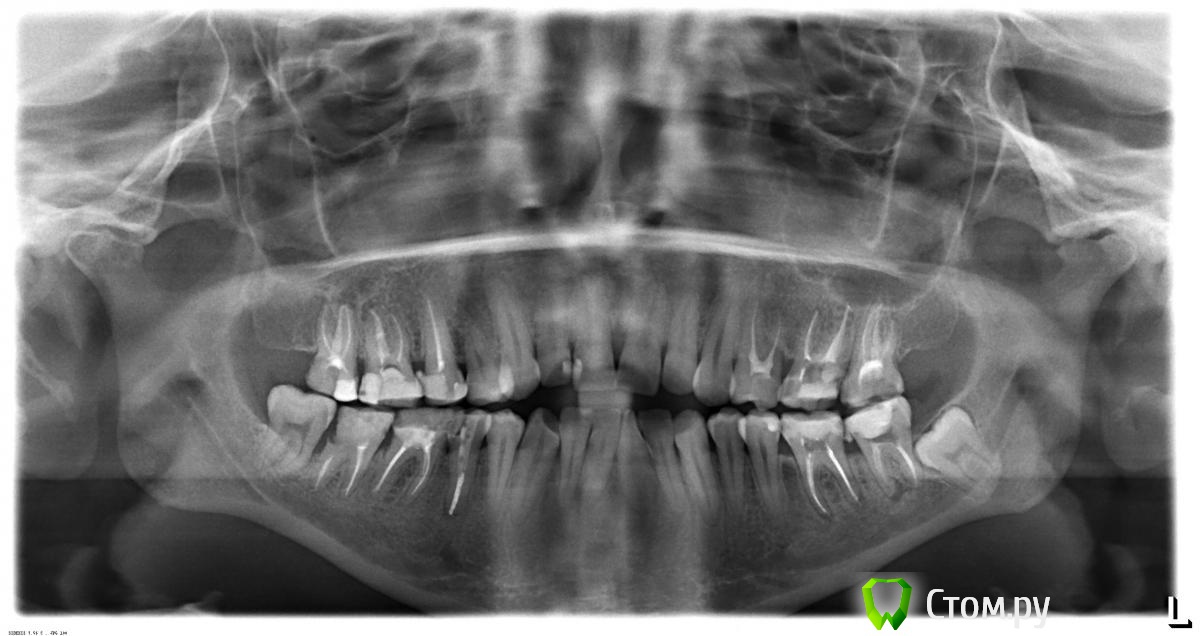

Гарриевич Опубликовано 16 ноября, 2014 Поделиться Опубликовано 16 ноября, 2014 Вам нужно еще поискать врача, а нам нужен ОПТГ Ссылка на комментарий

Stolga Опубликовано 17 ноября, 2014 Автор Поделиться Опубликовано 17 ноября, 2014 ОПТГ Ссылка на комментарий